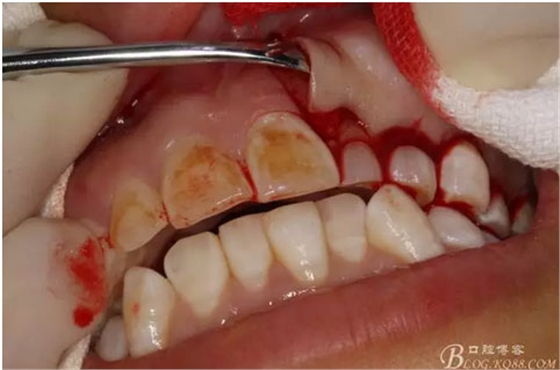

圖10.暴露出骨性隆起。骨質(zhì)表面光滑。

圖11.暴露出23的牙尖,牙尖垂直于唇側(cè)粘膜。建議拔除,患者同意。

圖12.用小骨鑿去除覆蓋在牙瘤表面的骨質(zhì)。發(fā)現(xiàn)牙瘤的包膜。